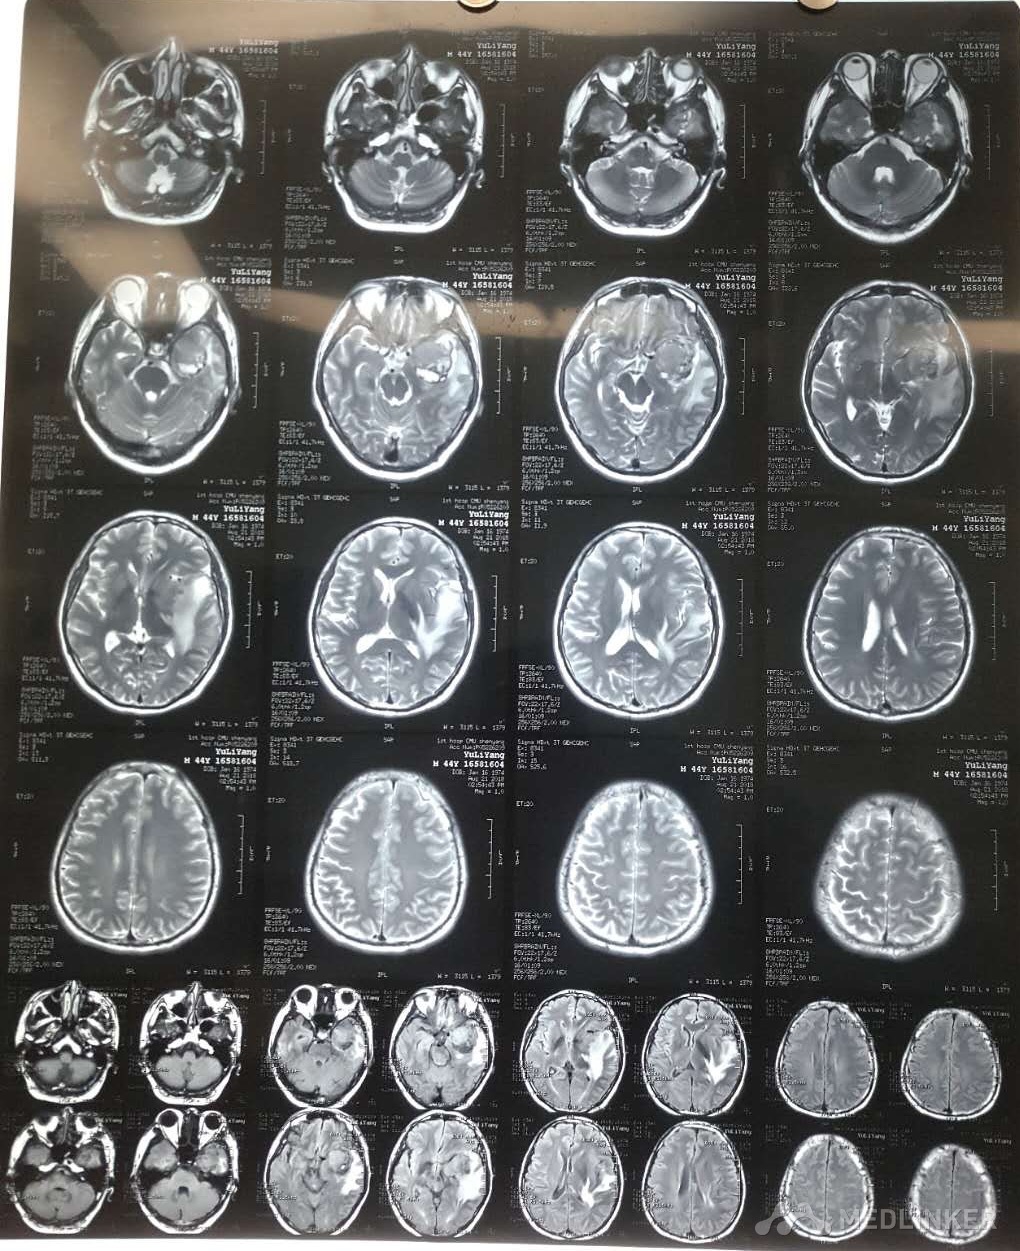

左侧颞叶占位

颞叶肿瘤

初步诊断:左侧颞叶占位,高血压,脑栓塞 确定诊断:左侧颞叶占位,高血压,脑栓塞 治疗:大脑深部病损切除术